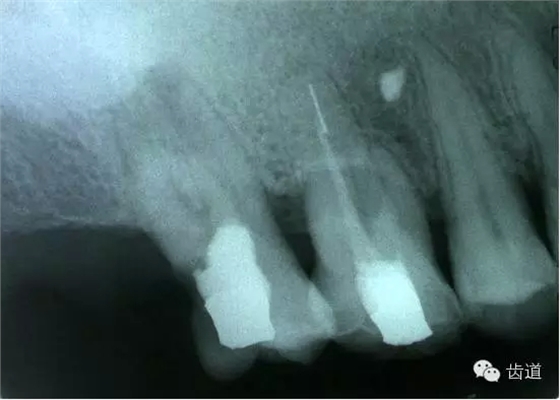

左上4鑄造樁側(cè)穿